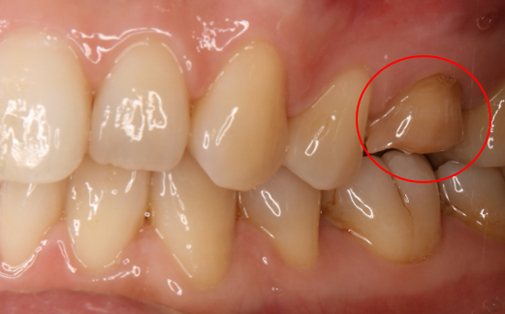

抜歯した親知らずを移植(1)

Before

After

左上の親知らずの歯を移植しました。20代前半の症例です。

ご自身の歯のため親和性が高く、移植後も不自由なく機能しています。